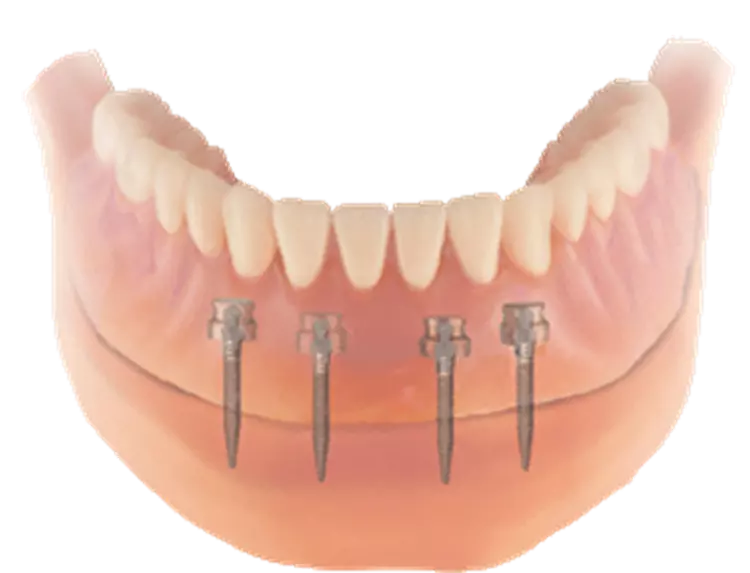

Das Ziel der Studie war es, die folgenden Aspekte zu untersuchen: Implantaterfolg, Überlebens- und Komplikationsraten, Implantat-Stabilitäts-Quotient, mundgesundheitsbezogene Lebensqualität und mögliche ableitbare Indikationen oder Kontraindikationen für die orale Rehabilitation mit Mini-Implantaten. Verwendet dafür wurde ein OHIP-G 14 Formular zur mundgesundheitsbezogenen Lebensqualität. Damit wird die psychische und physische Beeinträchtigung erfasst sowie die funktionellen Einschränkungen.

Aus der Summe der Einzelwerte können für den OHIP-G14 Werte zwischen 0 (keinerlei Beschwerden/ Beeinträchtigungen) bis 56 sein. Ein Patientenfragebogen wurde verwendet für die Beurteilung der Kaufähigkeit und der Reinigbarkeit der Prothesen mit Mini-Implantaten. Für die Überlebensrate wurde die Kaplan-Meier Methode angewandt. Verwendet wurden ebenfalls die Erfolgskriterien nach Albrektsson.

Weitere klinische Untersuchungen wurden durchgeführt, wie zum Beispiel die Messung der ST, BOP, PUS (ja/nein) und der LG. Weiter wurde eine Resonanzfrequenzanalyse durchgeführt zur objektiven Beurteilung der Osseointegration. Verwendet wurde dafür ein Osstell Mentor Messgerät.

Das Ergebnis ist ein ISQ Wert zwischen 1 und 100. Je höher der ISQ, umso stabiler ist das Implantat (Abb. 4 und 5). Nach Übertragung der gesammelten Daten in eine Excel-Tabelle und Aufbereitung des Datensatzes wurde zunächst die deskriptive Statistik berechnet. Der Chi-Quadrat-Test wurde zur Prüfung möglicher Korrelation angewandt.